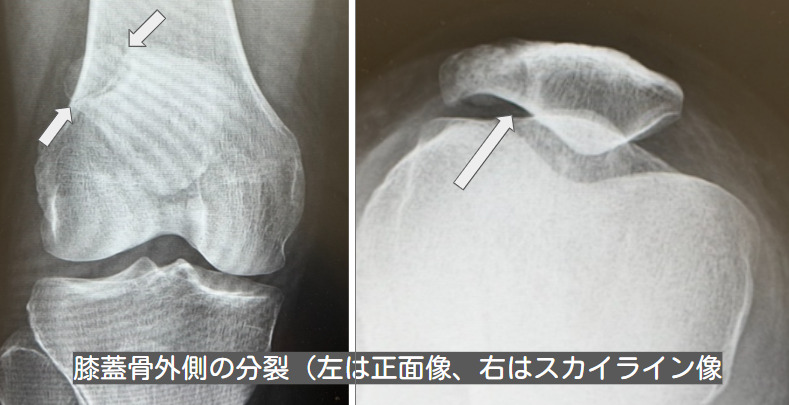

膝関節の単純X線前後像により、多くの場合、膝蓋骨近位外側部に分離がみられます。分裂膝蓋骨の分類としてはSaupe分類がよく知られています。Oohashiらの報告では、分離部が上外側部の2部である症例が83%と最も多く、次いで外側部の2部が12%、上外側部と外側部の3部が4%、上外側部の3部が1%でした。